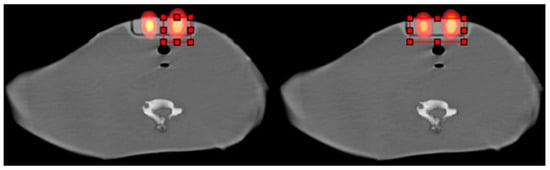

2.1. Method for Calculating Small Sizes of Volumes

2.1.1. Concept

2.1.2. MATLAB Calculations

2.1.3. Dependencies of the Gray-Level Histogram Technique